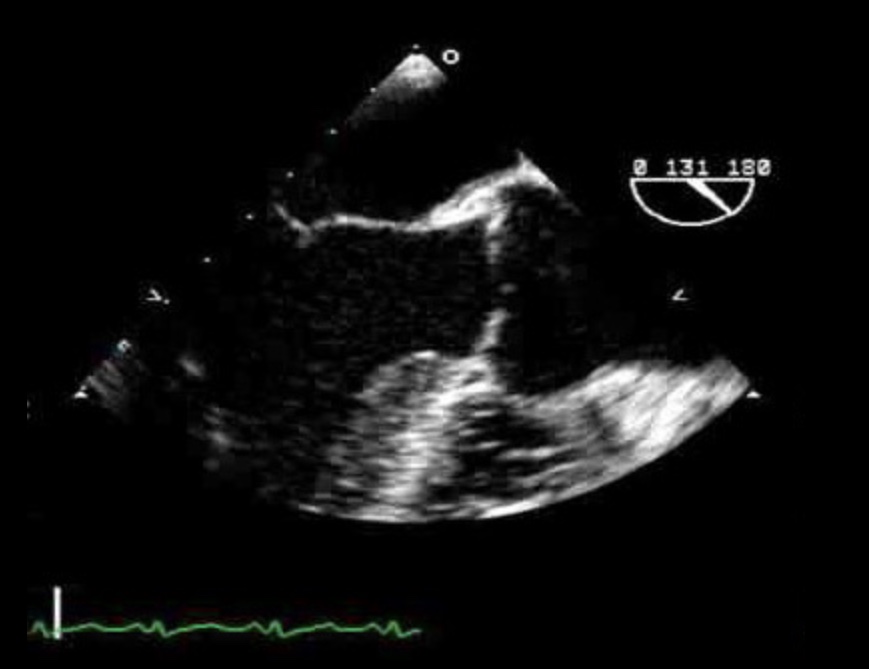

What view is this?

ME LAX

What transducer angle is used to obtain ME LAX?

120-140*